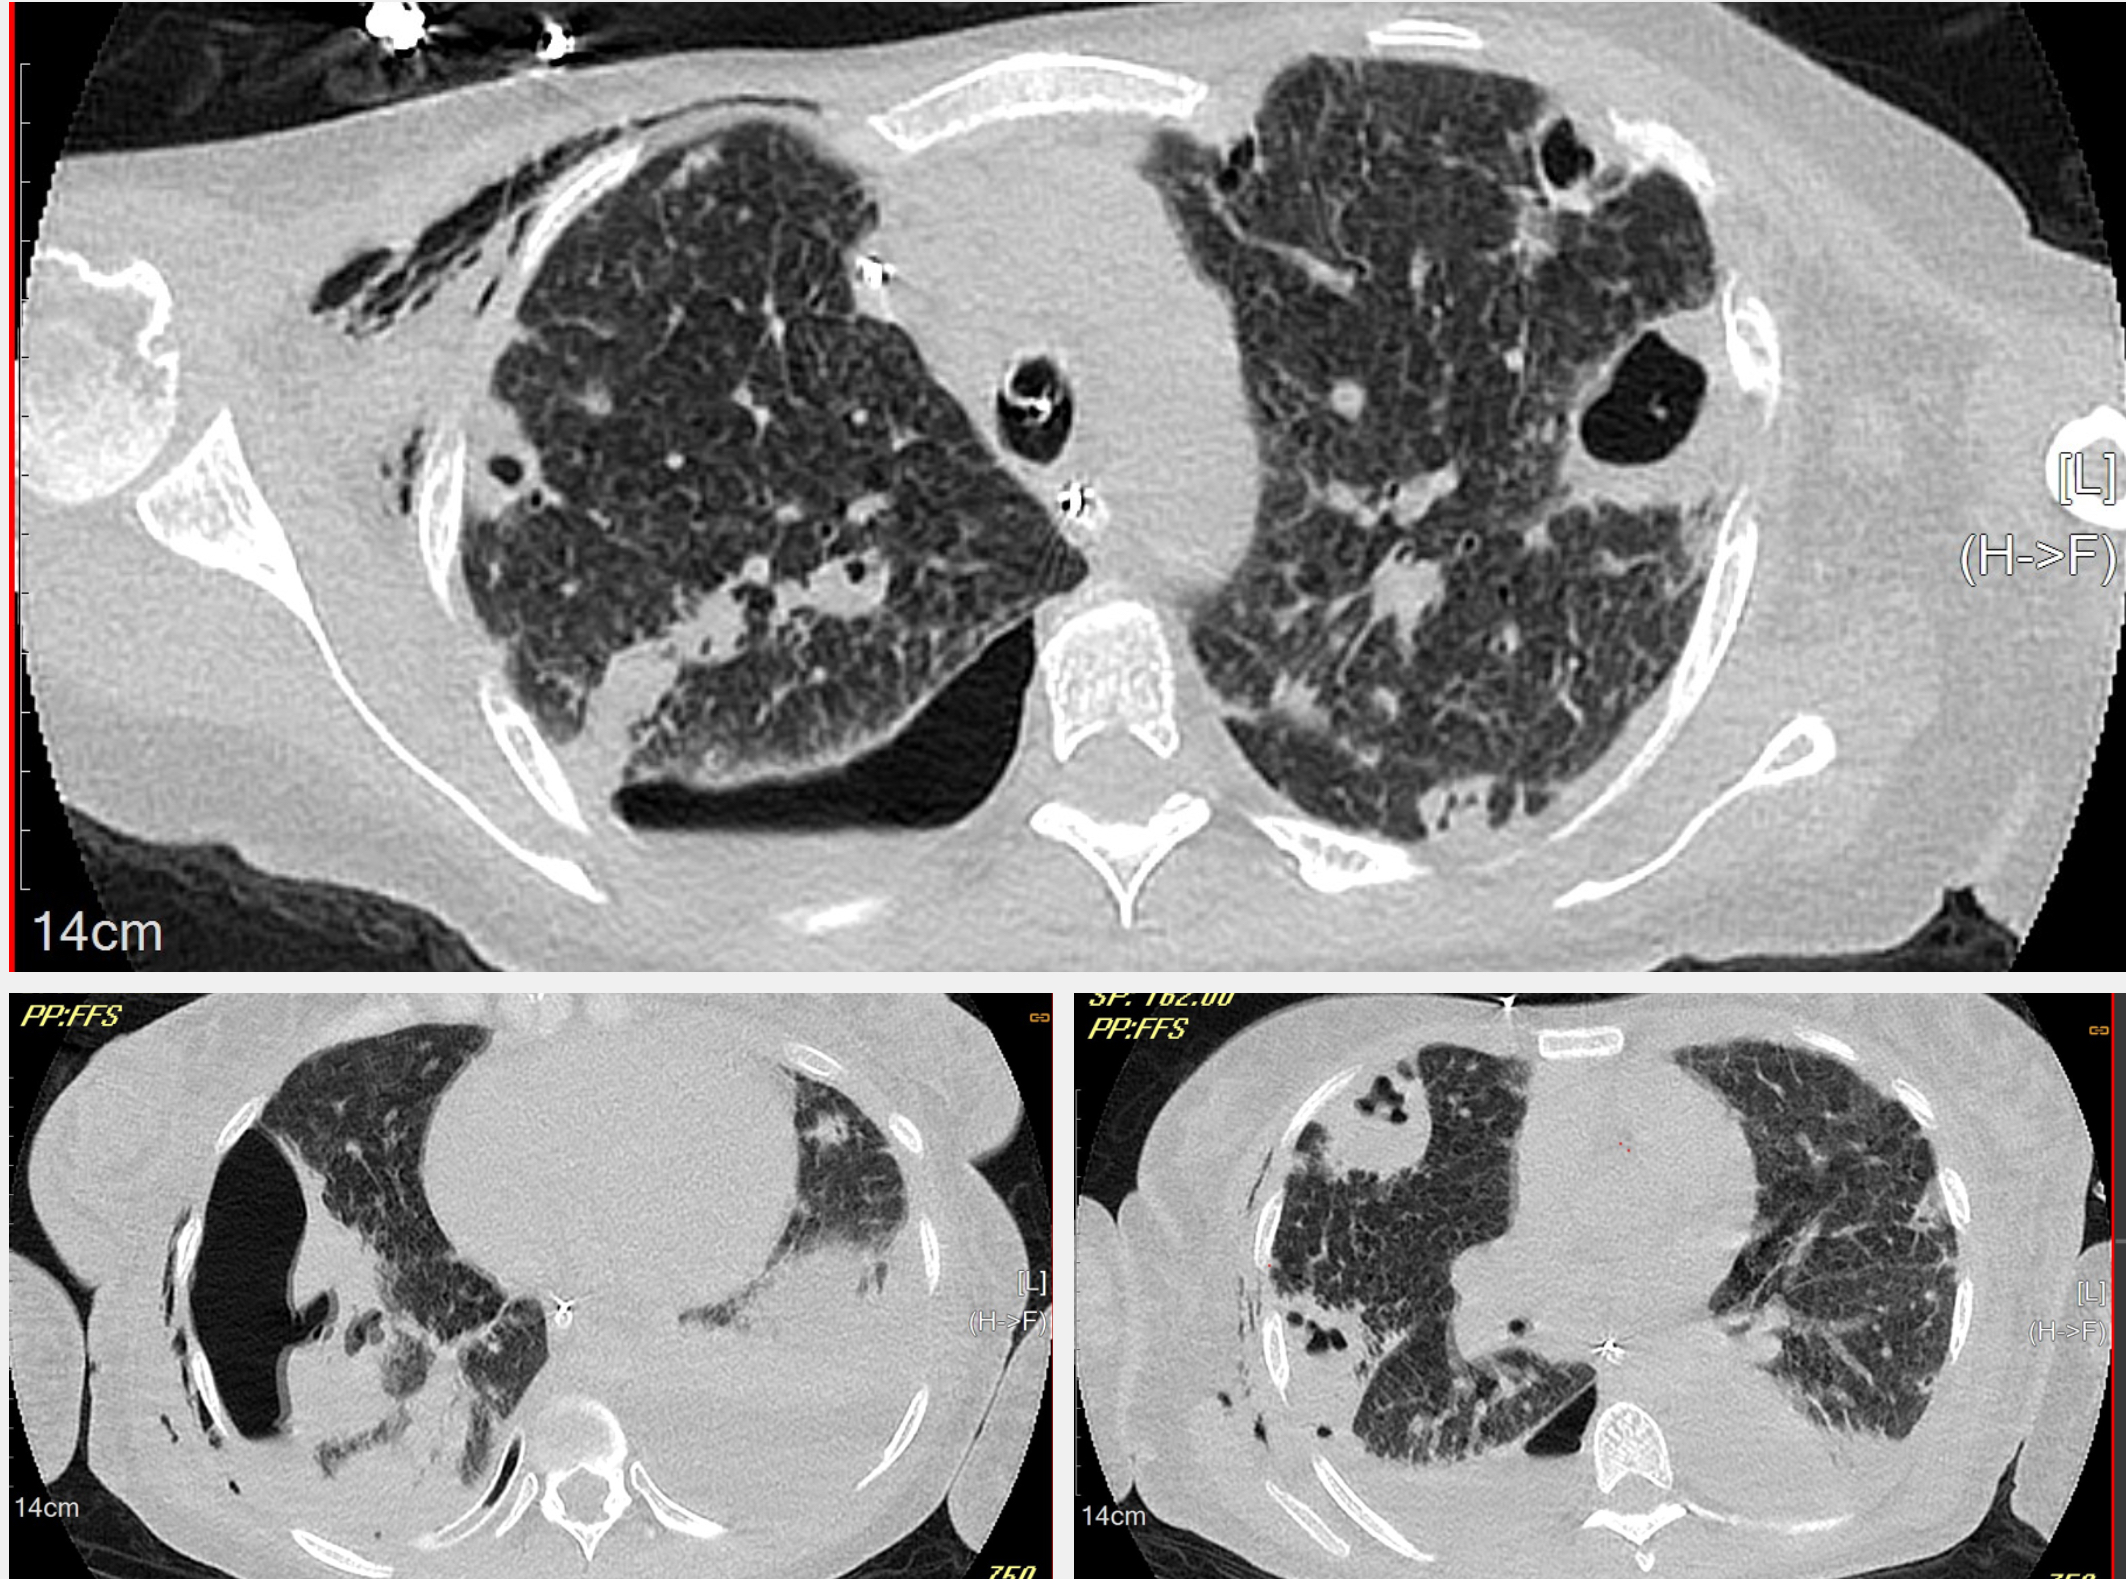

Immediate supplemental oxygen, IV fluids, pressors, and empiric antibiotics (piperacillin-tazobactam and vancomycin) were given. Laboratory studies showed elevated white cell count (WBC 18,700/μL), procalcitonin (287 ng/mL), CRP (29 mg/dL), and ESR (113 mm/h). Chest CT described bilateral pulmonary infarcts with extensive necrosis.

Due to a decline in the patient's respiratory status, repeat imaging was necessary, which showed a right lung abscess and empyema. She underwent video-assisted thoracoscopic surgery (VATS) with drainage and decortication.